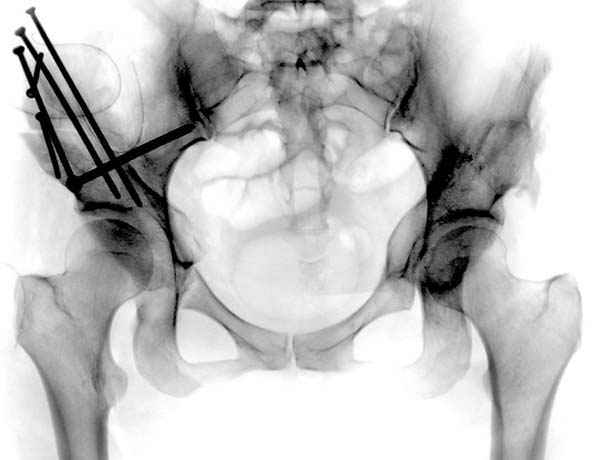

До операции #1

№ 1-3 до операции

№ 4-6 после операции при дисплазии тазобедренного

сустава